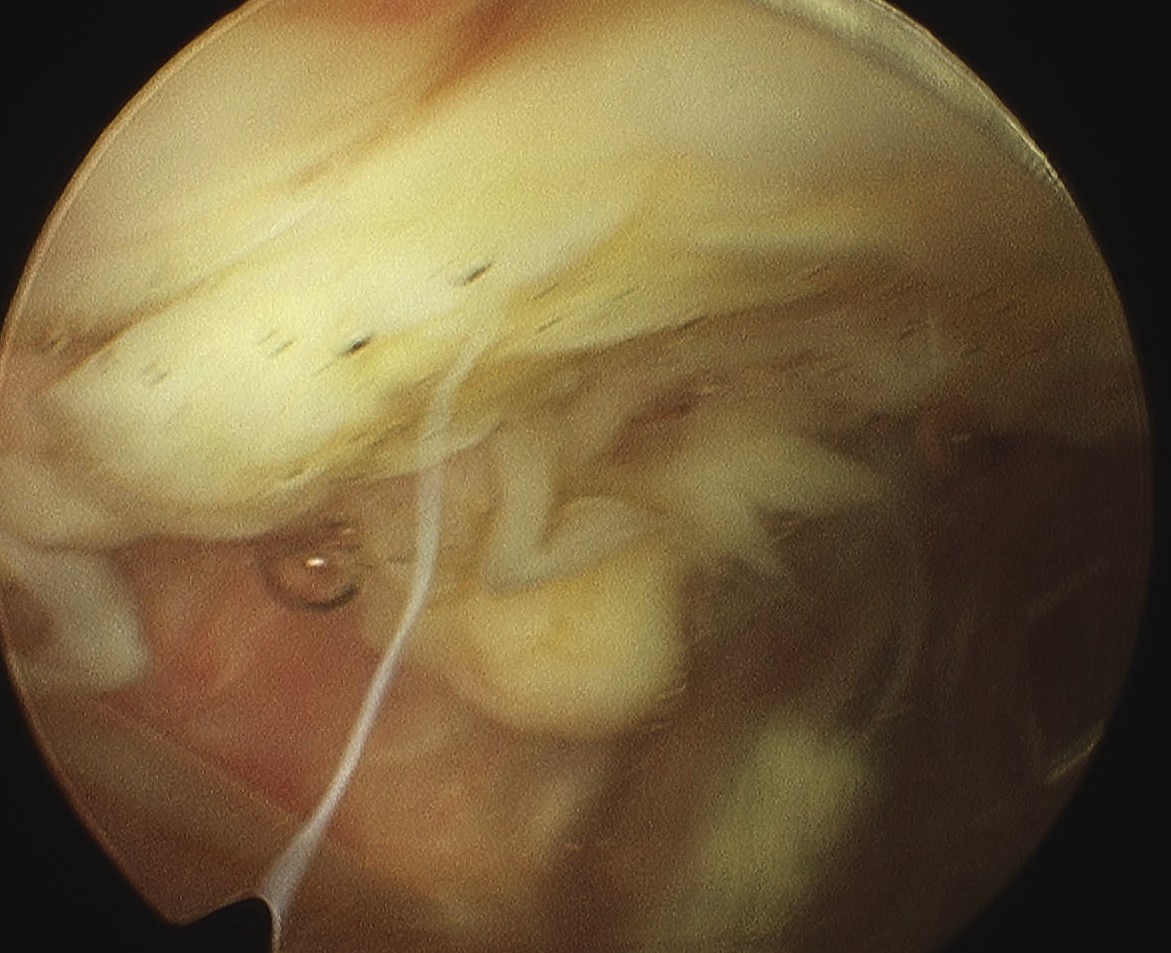

Arthroscopy

Patterns

Lateral facet - patella maltracking / trochlea dysplasia

Medial facet - patella dislocation and cartilage damage

Global - primary OA, patella fracture, obesity

Central trochlea - repetitive deep flexion

Medial facet OA Lateral facet OA